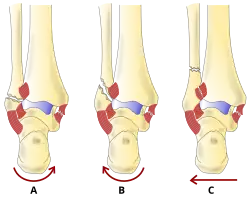

Anatomie fonctionnelle

La région de la cheville fait référence à l'endroit où la jambe rencontre le pied (région talocrurale)[4]. L'articulation de la cheville est une articulation charnière complexe et fortement contrainte composée de trois os : le tibia, le péroné et le talus[5],[6]. L'aspect porteur du tibia le plus proche du pied (appelé plafond) se connecte avec le talus. Cette articulation (où deux os se rencontrent) est principalement responsable de la flexion plantaire (déplacer le pied vers le bas) et de la dorsiflexion (déplacer le pied vers le haut)[6]. Ensembles, le tibia et le péroné forment une douille en forme de support connue sous le nom de mortaise, dans laquelle s'insère le talus en forme de dôme[7]. Le talus et le péroné sont reliés par un groupe solide de ligaments, qui soutiennent la face latérale de la cheville. Ces ligaments comprennent le ligament talo-fibulaire antérieur (ATFL) et le ligament talo-fibulaire postérieur (PTFL)[8]. Le ligament calcanéo-fibulaire (LFC), qui relie le péroné au calcanéum, ou os du talon, fournit également un soutien latéral. Le ligament deltoïde soutient la partie médiale de la cheville (la plus proche de la ligne médiane). Il empêche le pied de s'éverser excessivement ou de se tourner vers l'extérieur, tout en empêchant également le talus de tourner vers l'extérieur[8]. Les parties distales du tibia et du péroné sont reliées par un réseau de tissu conjonctif appelé syndesmose, composée de quatre ligaments et de la membrane interosseuse[8].